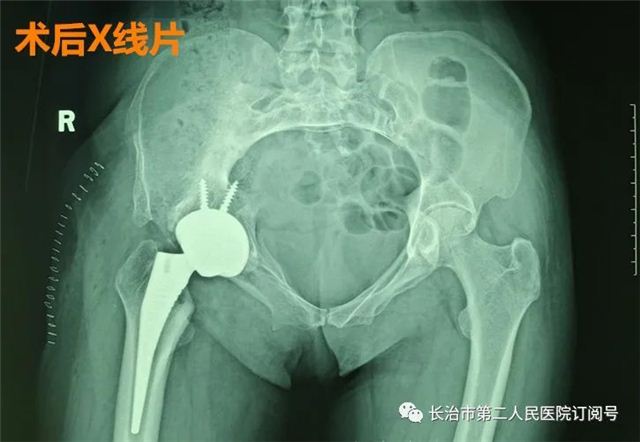

你能快速说出人体的关节名字吗? 相信有不少人 第一反应都会说出膝关节 有多少人知道人体最大的关节 髋关节呢? 髋关节 是人体连接躯干 和下肢的重要关节 人体直立行走时 依靠双侧髋关节支撑 如奔跑、行走、攀登等剧烈运动 需依靠髋关节 带动躯干完成不同动作 所以它也是人体最重要的关节之一 如果髋关节“叛变”了 问题就十分严重了 近日 48岁的张女士就因为“髋痛” 严重影响她的生活质量 究竟是怎么回事呢 据了解 在她15岁那年 右髋无故出现发热肿痛的症状 当地医院考虑 右髋关节感染予以行 右髋关节切开清创术 因引流口持久不愈合伴窦道形成 持续换药4个月后愈合出院 出院时右下肢已严重萎缩 右髋自发融合于屈髋40度 固定畸形 严重跛行步态 就这样 她忍受了33年之久 手术中,医生对于张女士截骨的位置和角度都需要极小心地判断,需要采用二次截骨法截断股骨颈,否则极易误伤髋关节周围的肌肉、神经和骨盆。由于她髋关节强直已有33年,髋周围肌肉长期废用性萎缩,对人工髋关节的保护能力很差,术后如何避免髋关节脱位是关键,需要医生术前严格仔细计划,术中准确把握髋关节假体安装角度;由于化脓性髋关节炎导致的骨性融合髋,原发致病菌是否已完全控制,术后有无可能原潜伏的病原菌死灰复燃导致假体感染发生,对于患者及医护人员提出极高考验。 科室介绍 长治二院关节外科一病区张鹏主任团队以“微创治疗、无痛手术、潇洒行走”的理念,将矫形外科、关节镜微创外科、运动医学的技术理念结合起来治疗各种关节疾病,是国内较早开展膝关节单间室置换术和肩关节置换术的科室之一。 门诊时间安排: 周三上午:李晓东院长 周一上午:张 鹏 周一下午:杨惠强 周二全天:王子江 周三全天:杨惠强 周四全天:张 鹏 周五全天:李向毅 地址:长治二院门诊二楼关节一诊室 联系电话:15635580253(张主任) 科室电话:0355-3126023 欢迎关注“骨关节疾病诊治”,微信号czey-gjwkybq